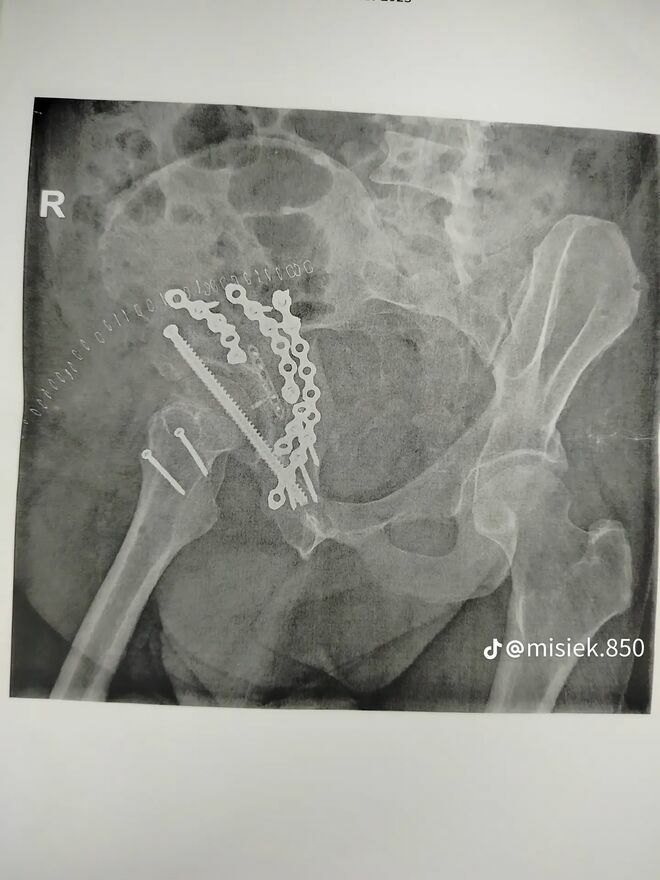

Niestety, jako pasażer uczestniczyłem w bardzo ciężkim wypadku samochodowym, który pozostawił mnie z poważnymi obrażeniami. Leczenie i rehabilitacja są kluczowe dla mojego powrotu do zdrowia, ale wiążą się z wysokimi kosztami, które przekraczają moje możliwości finansowe.